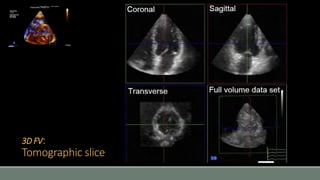

3D FV:

Tomographic slice

• #34 Using the 3D dataset, not exactly live then, a similar application is 2D tomographic slice rendering, where 2D views from any angle can be reconstructed, views that would be otherwise virtually impossible to get from standard acoustic windows. Volume rendering mode, where the 3D dataset will be cropped to show an area of interest.